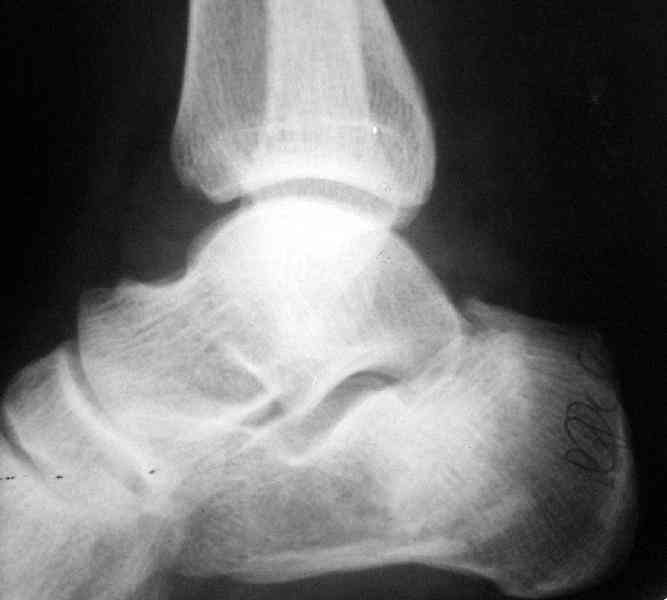

Re: Перелом пяточной кости

Какой предпочитаете доступ? Нет ли показательных рентгенснимков?

Открытый и закрытый способы лечения.